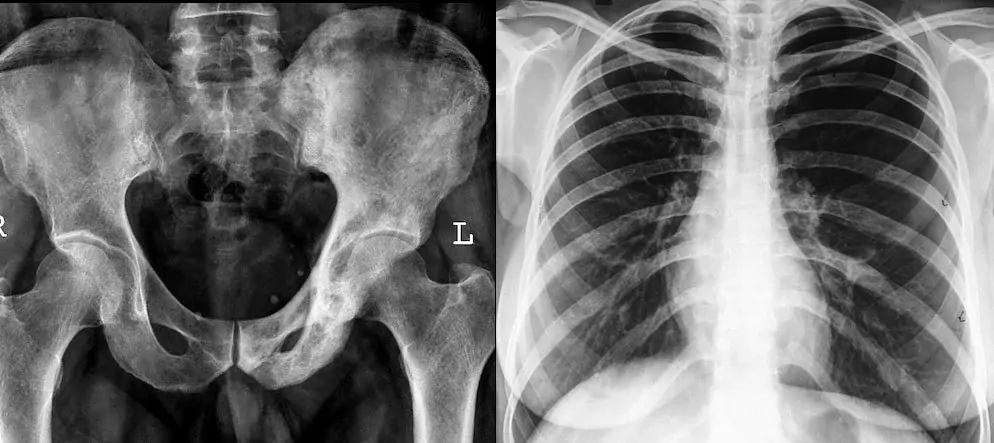

Digital X-ray films of different parts of the body are obtained. Most commonly these are of the chest, abdomen, kidney-ureter-bladder (KUB), spine and different bones and joints. We take radiographs of all parts of the body.

Siemens 500mA machine with image intensifier with an AGFA DX-M System.